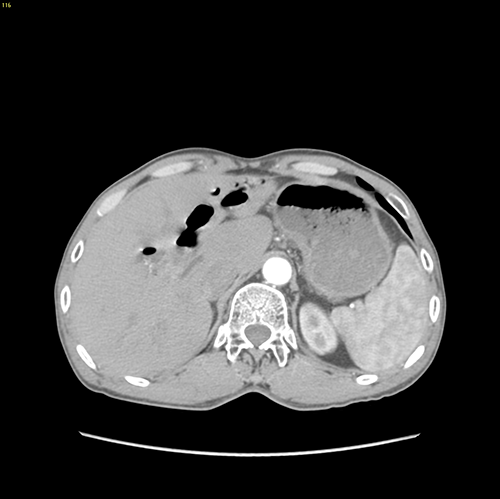

右肝内胆管结石、 胆管十二指肠瘘--S67肝切除、胆肠吻合、十二指肠瘘修补